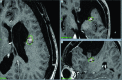

Case description: We present the case of a 41-year-old patient diagnosed with a left-sided frontal contrast enhancing lesion initially assessed as a tumefactive MS. Despite systemic treatment, the patient gradually developed signs of mass effect, which led to decompressive surgery. The initial microscopic evaluation demonstrated the presence of MS and oligodendroglioma; the postoperative evolution proved complex due to a series of MS-relapses and tumor recurrence. An ulterior revaluation of the samples for the purpose of this report showed an MS-concurrent anaplastic astrocytoma. We describe all relevant clinical aspects of this case and review the medical literature for possible causal mechanisms.